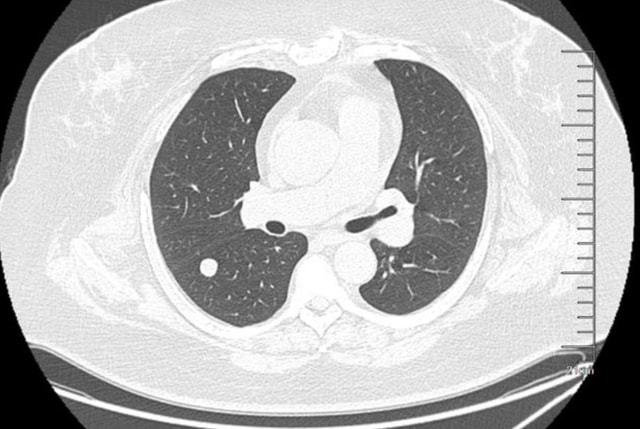

晚上睡觉的时候丈夫听到妻子总是咳嗽非常担心,于是带她去医院检查,医生检查之后,发现李大姐的肺部长出了5.3cm肺结节,这个结果可把李大姐和丈夫给吓坏了。

医生看出了李大姐一脸的忧愁,连忙跟她解释,5.3厘米的结节和肺癌可是相差甚远,李大姐的肺结节属于良性,只要后期按时定量吃药,避免熬夜,调整饮食,或许能够早日消散。

听完医生的一番话之后,李大姐忐忑的心终于安稳了下来,回到家之后李大姐按照医生的指示按时吃药,一段时间之后,没想到5.3厘米的结节竟然完全消失不见了,医生在了解到李大姐的生活习惯后,总结出的这几件事,或许对结节有帮助。